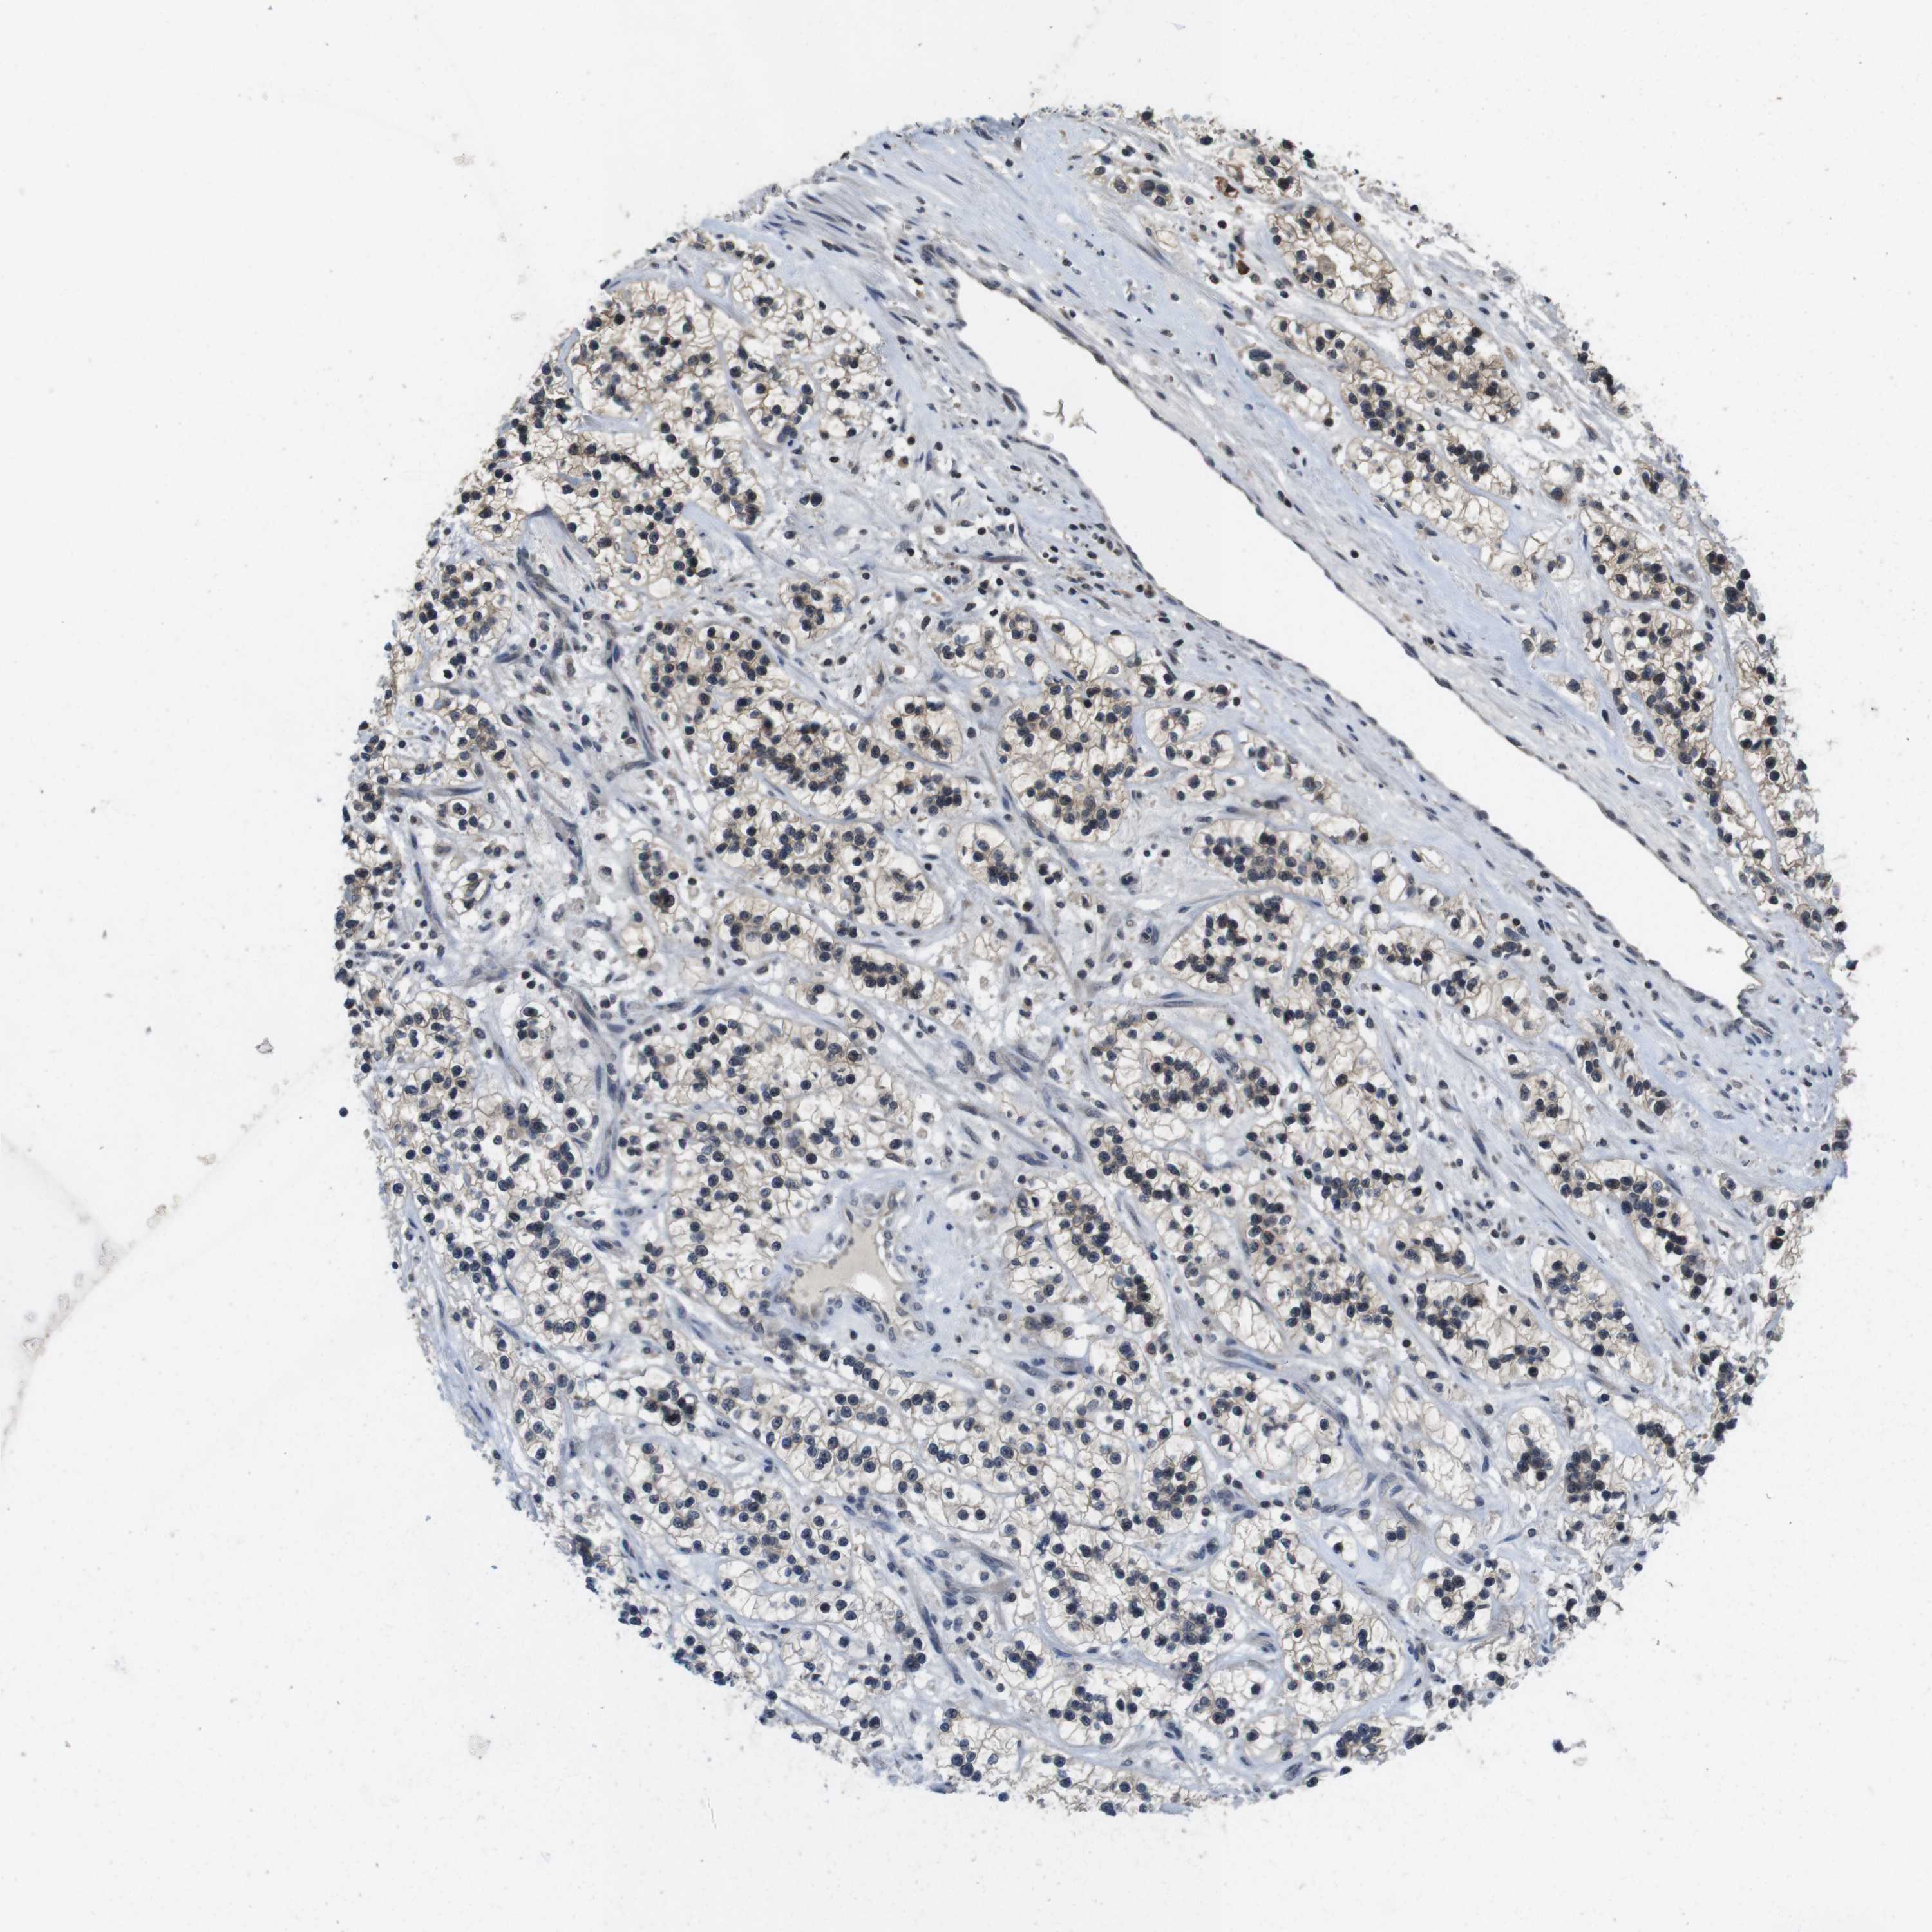

KIDNEY RENAL CLEAR CELL CARCINOMA (VALIDATION) - Interactive survival scatter ploti

The Survival Scatter plot shows the clinical status (i.e. dead or alive) for all individuals in the patient cohort, based on the same data that underlies the corresponding Kaplan-Meier plots. Patients that are alive at last time for follow-up are shown in blue and patients who have died during the study are shown in red.

The x-axis shows the expression levels (FPKM) of the investigated gene in the tumor tissue at the time of diagnosis. The y-axis shows the follow-up time after diagnosis (years). Both axes are complimented with kernel density curves demonstrating the data density over the axes. The top density plot shows the expression levels (FPKM) distribution among dead (red) and alive patients (blue). The right density plot shows the data density of the survived years of dead patients with high and low expression levels respectively, stratified using the cutoff indicated by the vertical dashed line through the Survival Scatter plot. This cutoff is automatically defined based on the FPKM cutoff that minimizes the p-score. The cutoff can be changed by dragging the vertical line or by entering a cutoff value in the square labeled "Current cut-off".

Under the Survival Scatter plot the p-score landscape (black curve; left axis) is shown together with dead median separation (red curve; right axis). Dead median separation is the difference in median mRNA expression between patients who have died with high and low expression, respectively. It is calculated as follows: median FPKM expression of dead patients with high expression - median FPKM expression of dead patients with low expression. This is intended to aid the user in visually exploring custom cutoffs and the associated p-scores and dead median separation.

Individual patient data is displayed and can be filtered by clicking on one or more of the category buttons on the top of the page. Categories describing expression level and patient information include: high, low, alive, dead, female, male and tumor stages. The scale of the x-axis can be toggled between linear and log-scale by clicking on the "x log" button. Mouse-over function shows TCGA ID, patient information and mRNA expression (FPKM) for each patient.

& Survival analysisi

Kaplan-Meier plots summarize results from analysis of correlation between mRNA expression level and patient survival. Patients were divided based on level of expression into one of the two groups "low" (under cut off) or "high" (over cut off). X-axis shows time for survival (years) and y-axis shows the probability of survival, where 1.0 corresponds to 100 percent.

FADD is not prognostic in Kidney Renal Clear Cell Carcinoma (validation)

: 24.98

Average pTPM 28.0

Number of samples 100